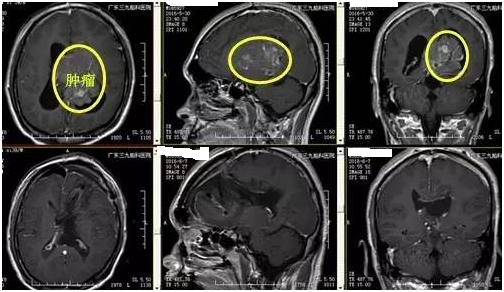

陈男子,39岁,3个月前开始头晕头痛,在卫生院抓药吃后有所缓解,近1个月症状加重伴恶心、呕吐、肢体乏力,为求进一步治疗来我院就诊。入院后完善相关检查,提示:肿瘤位于脑室内,钙化明显,形态不规则,肿瘤最大径8.1cm,双脑室不同程度扩大,诊断:双侧侧脑室巨大占位性病变;梗阻性脑积水。由神经外一科张良教授主刀切除脑室内肿瘤,解除脑积水,经系统康复治疗后,患者症状缓解出院。术后病理提示中枢神经细胞瘤,WHO II级。

▲手术前后对比